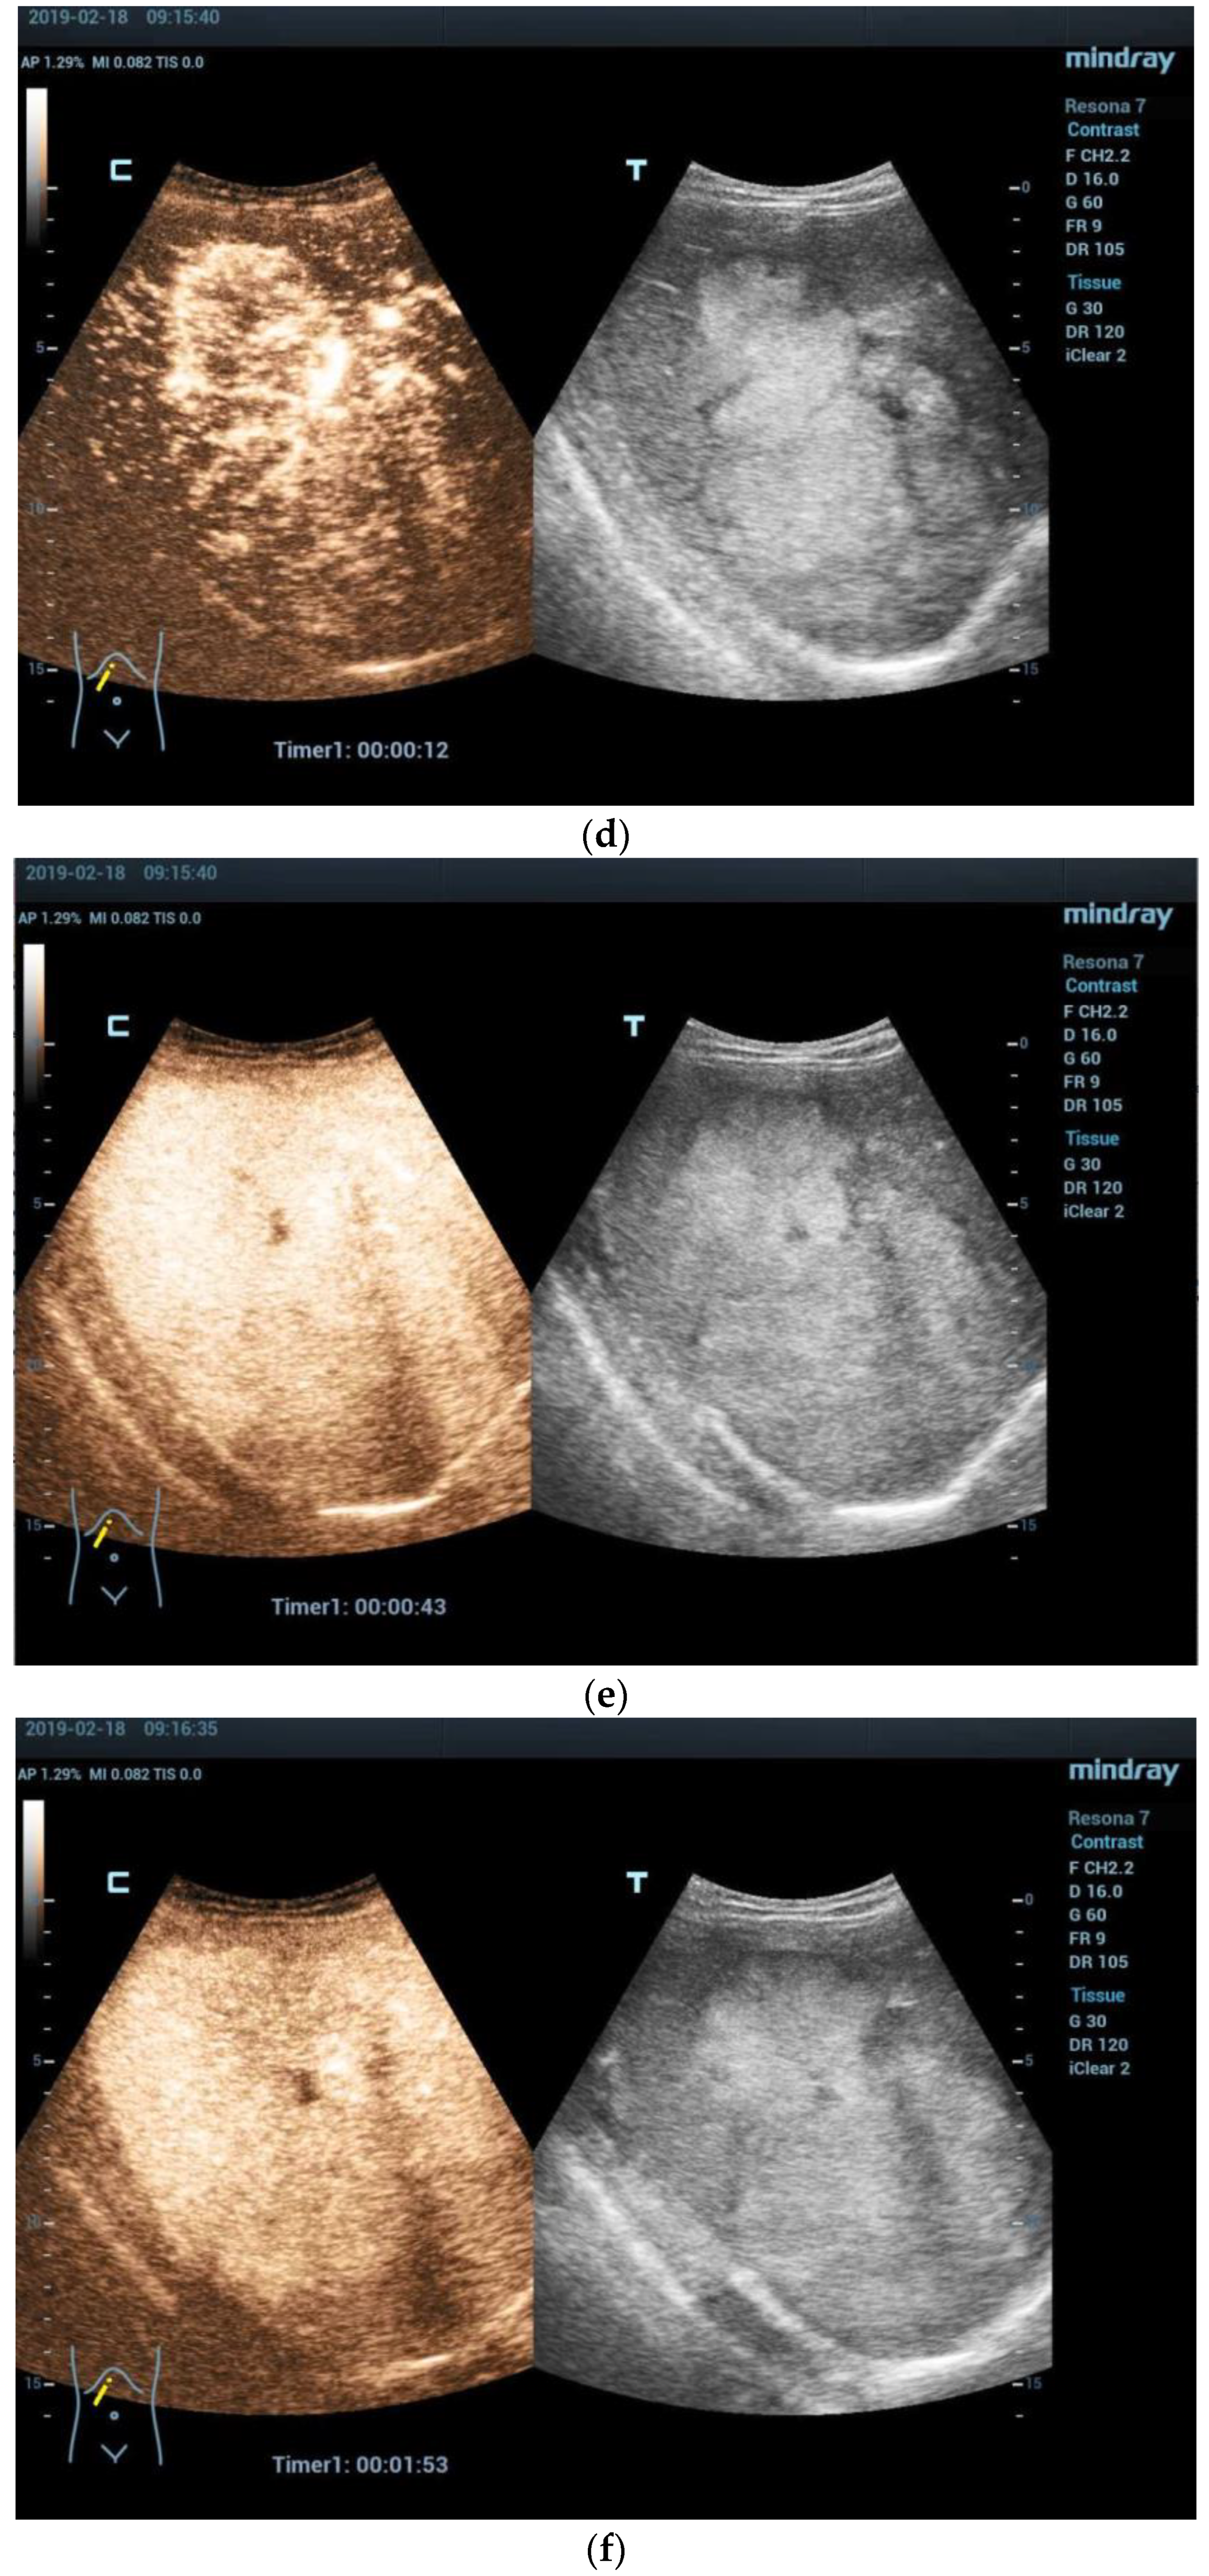

- Anupindi, S.A.; Biko, D.M.; Ntoulia, A.; Poznick, L.; Morgan, T.A.; Darge, K.; Back, S.J. Contrast-enhanced US Assessment of Focal Liver Lesions in Children. Radiographics 2017, 37, 1632–1647. [Google Scholar] [CrossRef]

- Wang, G.; Xie, X.; Chen, H.; Zhong, Z.; Zhou, W.; Jiang, H.; Xie, X.; Zhou, L. Development of a pediatric liver CEUS criterion to classify benign and malignant liver lesions in pediatric patients: A pilot study. Eur. Radiol. 2021, 31, 6747–6757. [Google Scholar] [CrossRef] [PubMed]

- McCarville, M.B. Contrast-enhanced sonography in pediatrics. Pediatr. Radiol. 2011, 41 (Suppl. S1), S238–S242. [Google Scholar] [CrossRef] [PubMed]